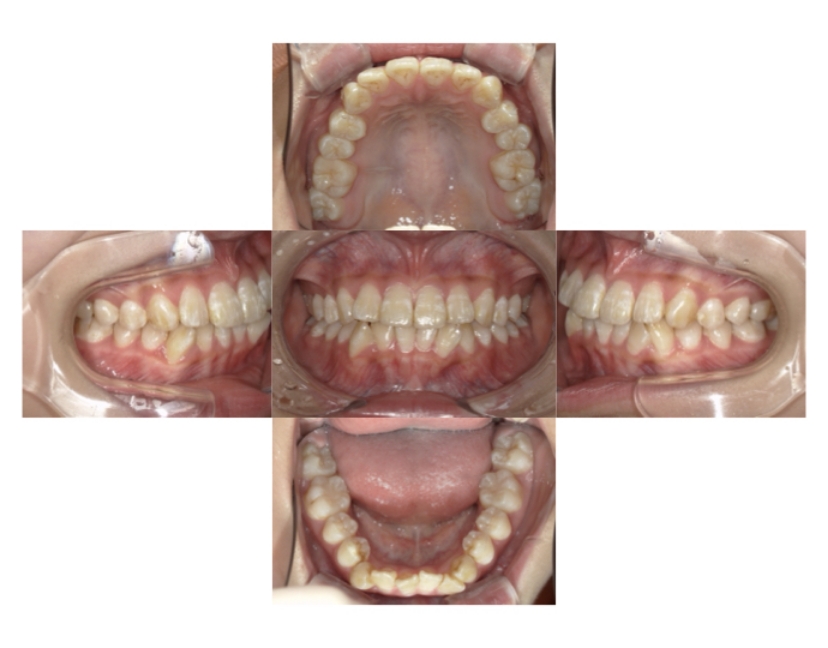

症例2

上下顎前突、叢生

抜歯

ブラケット矯正

上下顎前突、叢生(上下出っ歯、上下の前歯のガタガタ)のケースです。

装置はラビアル(上下表側)で、上下顎の小臼歯を4本抜歯を行っています。抜歯したスペースを使って、上下の前歯の後方移動と叢生(ガタガタ)の改善を行っています。

主訴 前歯のガタガタと口元がでているのが気になる。

年齢・性別 30歳 女性

お住まいの地域 東京都大田区

治療方針 抜歯スペースを利用して上前歯の叢生(ガタガタ)と口元突出の改善

抜歯部位 上下顎左右第一小臼歯

使用装置 ラビアル(上下表側)、顎間ゴム

治療期間 1年11か月

治療回数 13回

リテーナー クリアリテーナー

BEFORE